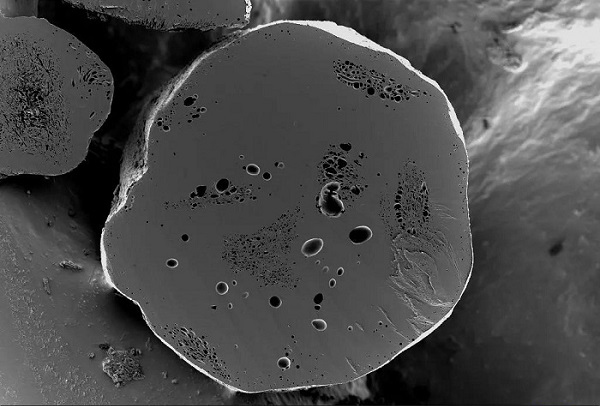

緩釋藥顆粒內部孔隙結構觀察